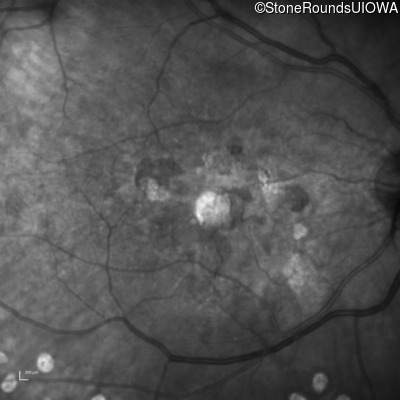

Malattia Leventinese (IIJ)

Malattia Leventinese (IIJ)

This 43 year old woman has experienced a gradual reduction in her central vision for the past 3 years.

| Malattia Leventinese | EFEMP1 | Arg345Trp CGG>TGG | AD |